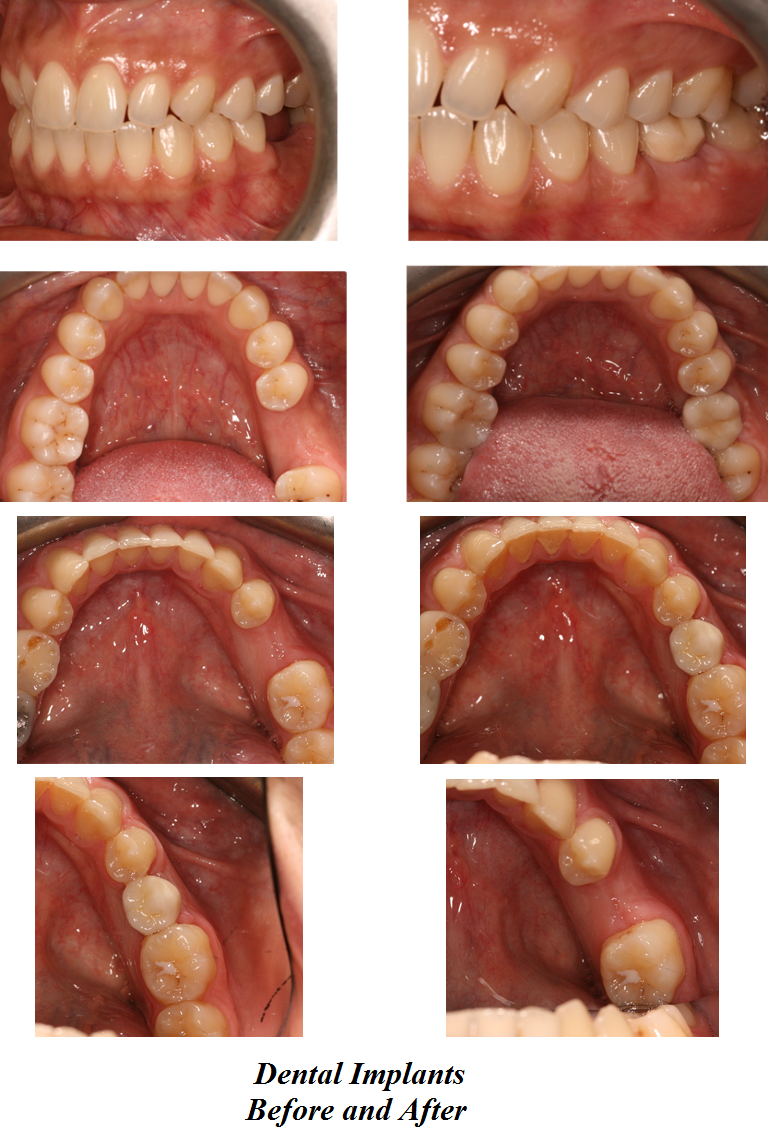

Here at Aesthetic Dental Zone we embrace new concepts, guided implant surgery provides a solution where doctors can plan an implant virtually, and then accurately place an implant in the safest, predictable and efficient manner.

With guided surgery, we place the implant for the best aesthetic result and can predict accurately how much room will be needed for the crown and for any veneered superstructure that may go over the abutment.

From a single missing tooth to an edentulous jaw. It aids your Doctor to diagnose, plan the treatment and place your implants based on restorative needs and surgical requirements.

Following an initial Implant Consultation and CBCT scan (3D Scan of your jaw) we can get to work on your specific Implant case.Guided Implant Surgery takes away the need to be too invasive when placing your dental implants.

It is extremely accurate, more comfortable and the healing time is reduced.Guided Implant Surgery is a state of the art technology, trust in us to make your implant process as simple and easy as possible.